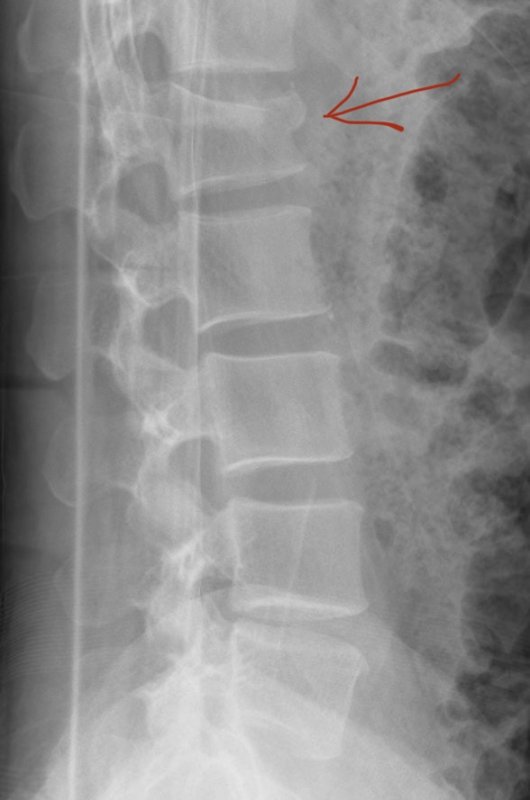

View attachment 168846MRI confirmed what appeared on my X-ray …compression fracture of my L1 vertebrae. I need to wear a back brace for 9 weeks. Luckily I have very little pain but no bike riding or strenuous activities for 9 weeks. 😩

Wet conditions. Bad line choice. Me go boom. Back go crack. Walked out of the woods on my own but then … the nightmare continued.Synopsis of what happened?